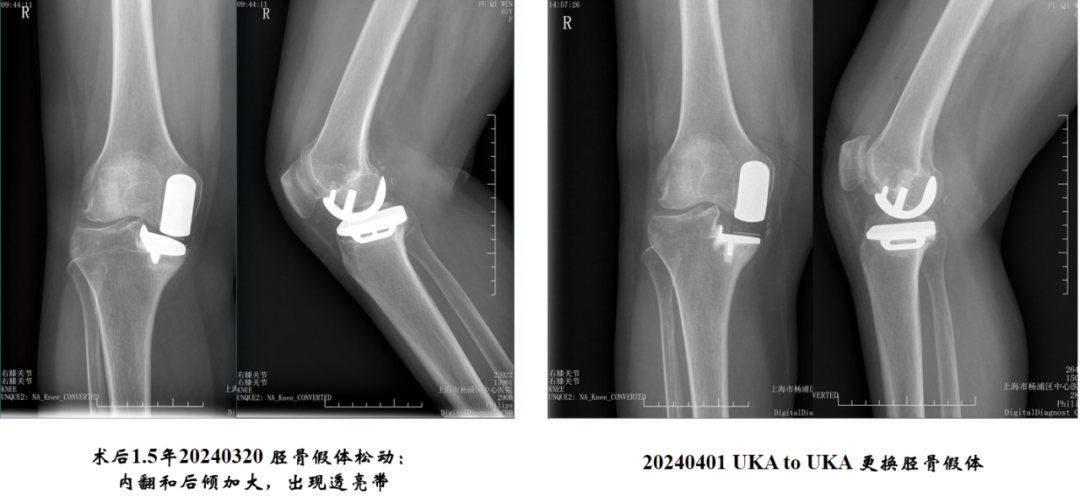

胫骨平台内外覆盖(冠状位)

胫骨假体对胫骨截骨面的覆盖:内侧缘齐平,假体完全覆盖胫骨平台。

胫骨平台内侧突悬

胫骨假体对胫骨截骨面过度覆盖:内侧缘突悬>2mm,垂直截骨宽度不足。

胫骨假体对胫骨截骨面过度覆盖:内侧缘突悬>2mm ,假体选择大了一个号。

胫骨平台内侧覆盖不良

胫骨假体对胫骨截骨面的覆盖不足:内侧缘覆盖不足。